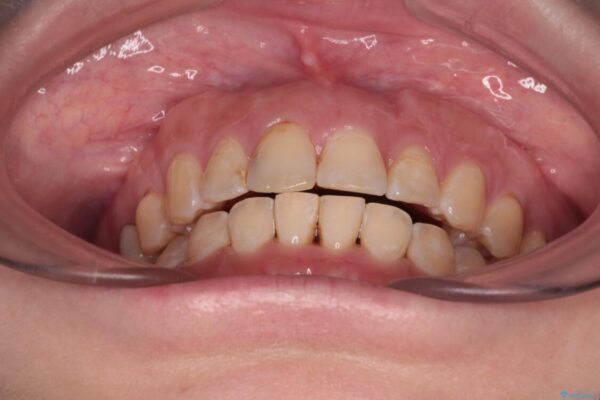

飛び出た上の前歯を気にして来院された患者様です。

奥歯の咬み合わせは、上顎歯列が理想的な一よりも数mm前方にある状態でした。

治療前

• 【モニター】飛び出た前歯を整えたい ワイヤー矯正治療 治療前画像